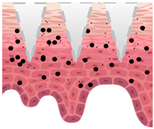

| Types of MNs | Solid MNs | Coated MNs | Dissolving MNs | Hollow MNs | Swellable MNs |

|---|---|---|---|---|---|

| Just before insertion |  |  |  |  |  |

| After application |  |  |  |  |  |

—MN loaded with active ingredients;

—MN loaded with active ingredients; —solid needle;

—solid needle; —dissolving/swellable needle;

—dissolving/swellable needle; —stratum corneum.

—stratum corneum.| Material | Characteristics | Cosmetic Benefits | 3D Printability |